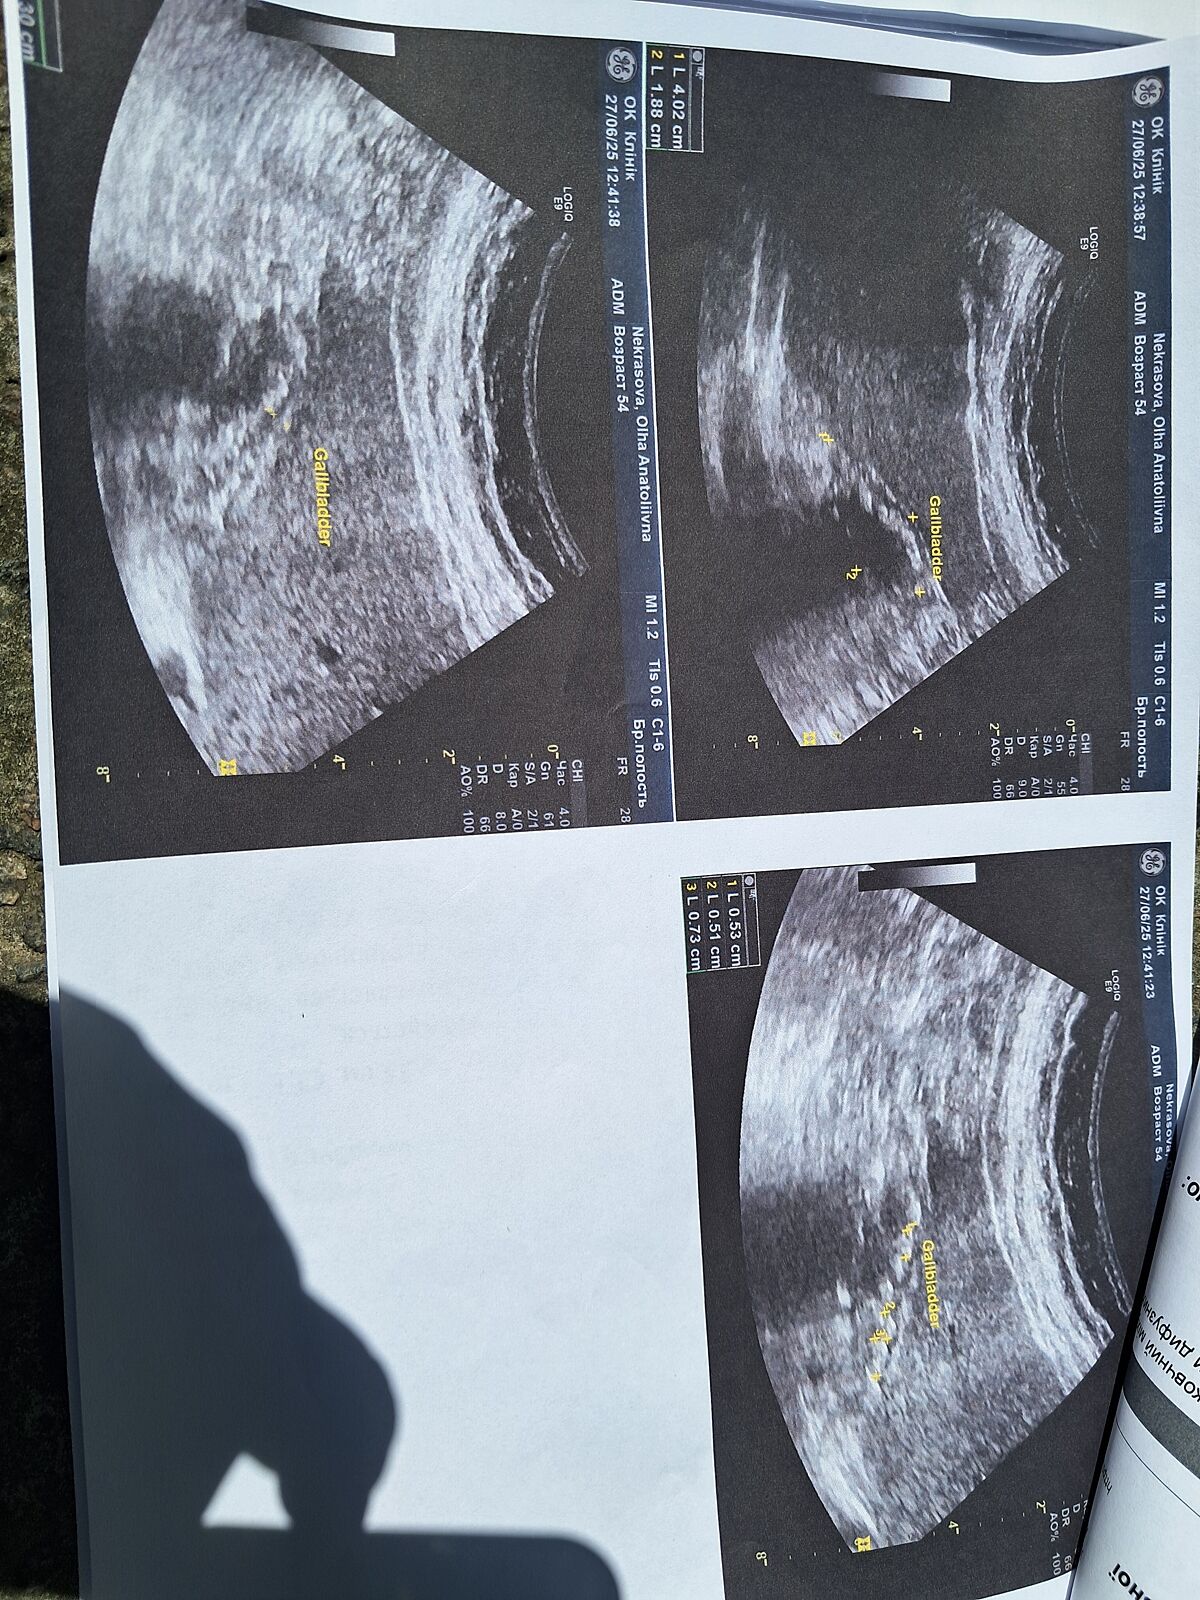

Добрый день. Обследовалась по поводу болей в животе, на УЗИ обнаружили, что у меня отключенный желчный, не работает, забит камнями,гастроентеролог говорит, что нужно удалять желчный. Может кто-то был в такой ситуации, как это все проходит, если лапаро. И нужно ли удалять, действительно ли это бомба замедленного действия. Подскажите врача, можно в личку, Киев

Сколько камней на снимке узи?

Да, какое-то странное узи, непонятно , там пару камней или 20. Автор , но учитывая, что камни мелкие (могут забить проток ) и у вас есть дискомфорт, я бы удалила. Я уже лет 15 с двумя камнями , но у меня они крупные , когда не переедаю , не беспокоят.

Но в любом случае сходила бы ещё на УЗИ. Мне тоже один раз сказали , что желчный у меня отключён , но это оказалось неправдой, просто узист решил, что так я соглашусь на операцию

Камни мелкие их многовато, да, но при таком размере СТОИТ принимать препараты с урсодезоксихолевой кислотой с целью их растворения.